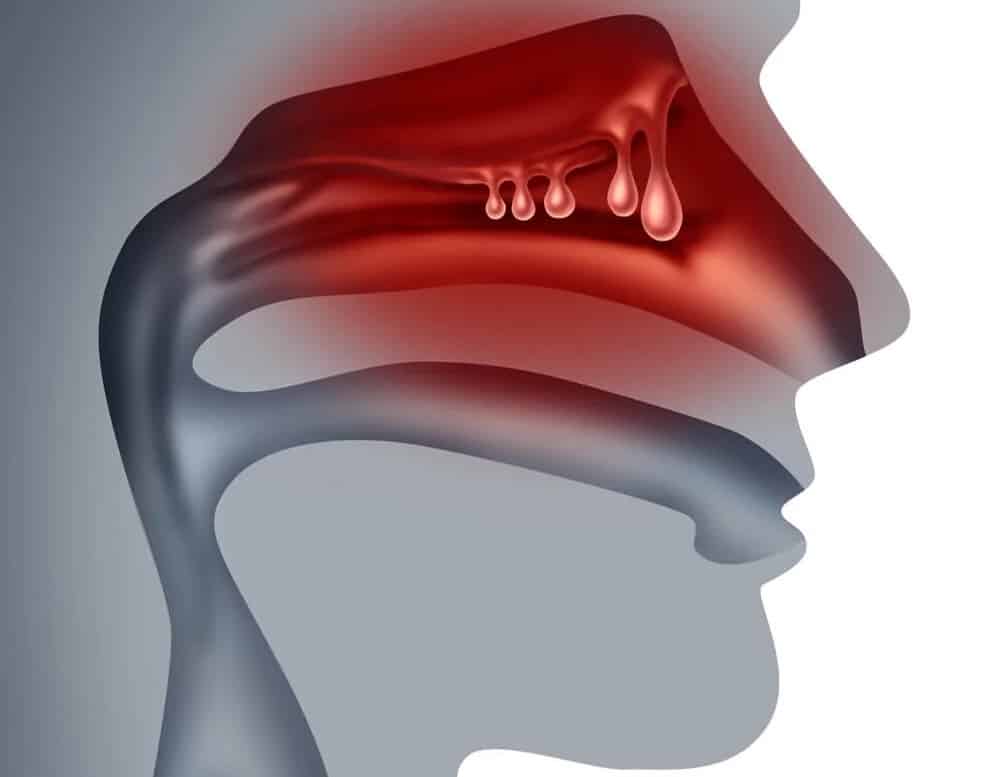

- Diagnóstico y tratamiento de rinitis, sinusitis y desviación del tabique nasal

3. ¿La sinusitis crónica tiene cura?

Sí, con un tratamiento adecuado que puede incluir medicamentos, irrigaciones nasales o cirugía en casos graves.